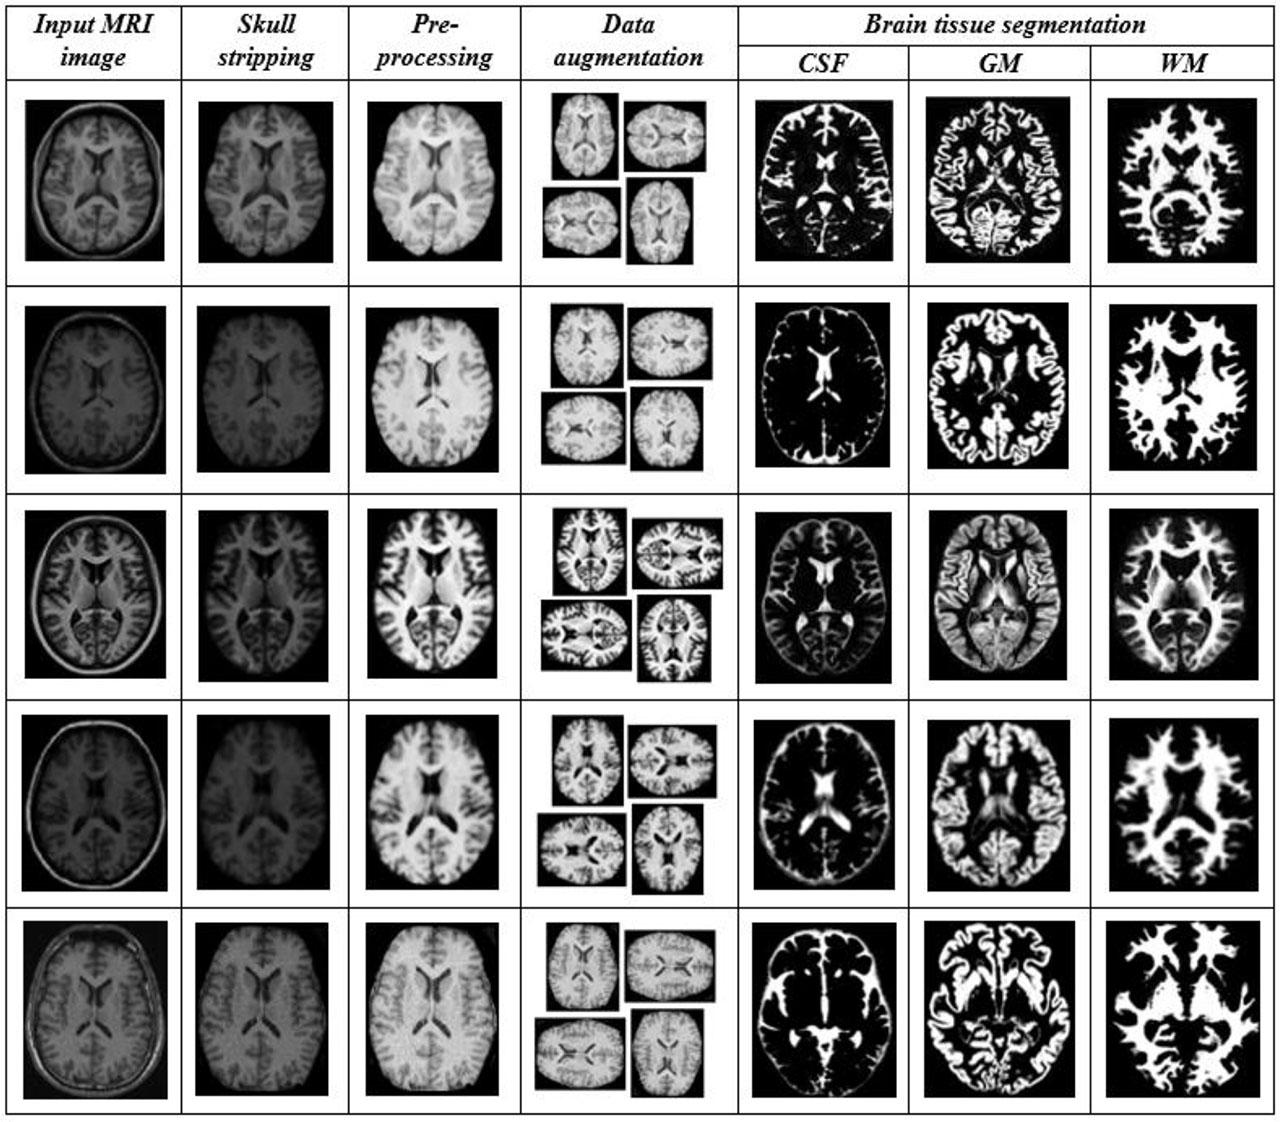

Fig. 1.